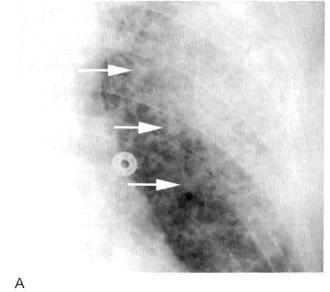

肺实变的患者中,充气的支气管在平片或CT上都能看到,在不透光的肺实质衬托下显示为透光区(图1)。这一征象称为空气支气管征。

图1 实变:均匀致密影、纹理遮盖,空气支气管征和CT血管造影征

A. 肺水肿所致的右肺实变。可见双侧实变肺内 空气支气管征,肺血管模糊;B.右肺中下叶肺炎患者增强CT显示病变区均匀实变、肺体积保持不变,空气支气管征(黑色箭头)和致密学观影(白色箭头),其密度高于邻近实变肺组织(即“CT血管造影”征)